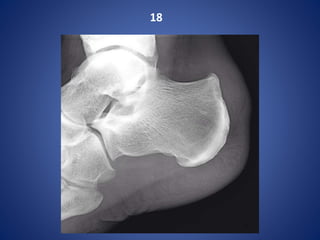

18

Haglund syndrome - bony prominence of the posterosuperior aspect of the calcaneum (Haglund

deformity) with marked surrounding soft-tissue oedema due to insertional Achilles tendonosis

and retrocalcaneal bursitis.

Haglund syndrome